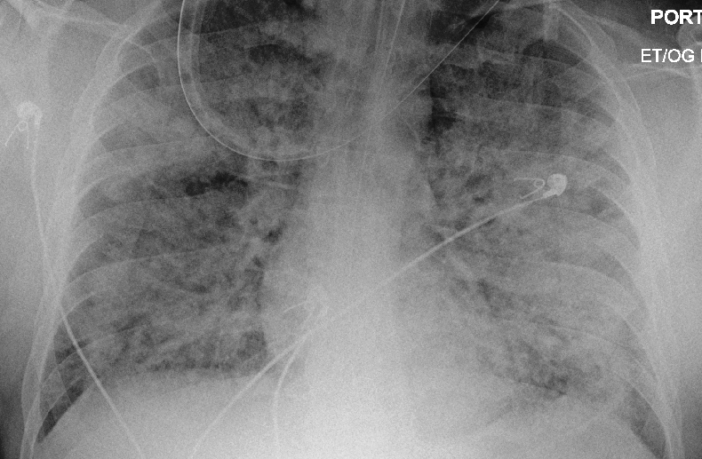

Young people could get seriously ill too. They could suffocate to death when their lungs fill with fluid from acute respiratory disease symptom, and they can’t breathe any more.   Their minds would grow dim as their lives ebbed away. We could spend the rest of our lives grieving a loved one. Just because we weren’t that concerned how we would know if we had COVID-19.

Preview Image: Person with Severe ARDS